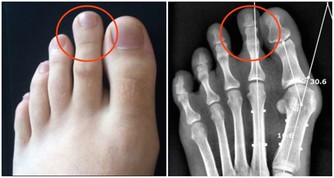

“降三高”類藥

這些藥物以壓以降以抑制以主,雖然能暫時地控制症狀,但從來不能完全治好,病人要終生服藥。人體的陽氣是自然向上升發的,但這種治法卻逆了生命的趨勢向下壓,則陽氣不能自然升發;“三高”本來即屬陽氣不足,邪氣內入而致,結果因為“三高人群”長期大量服用西藥後,反倒令陽氣更加匱乏,導致身體越發虛弱。